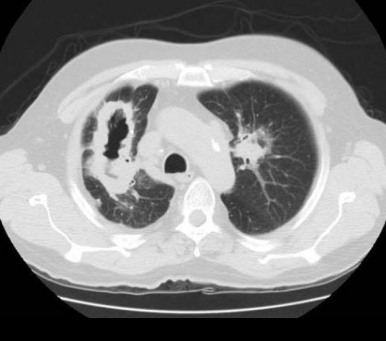

■ Cavitary lesion / nodule (공동성 병변)

§ Solitary cavitary nodules (단일 공동성 결절)

- 공동성 병변은 thick, irregular 한 wall

- 내부에 solid mural component가 존재할 수도 있음.

- 벽의 두께에 따라 4mm 이하 = benign, 15mm 이상일 경우 malignant의 가능성이 높음

- Spiculated(침상형)의 경계를 가질경우 malignant의 가능성 높음

→ ADC와 SCC 모두 공동을 형성 할수 있으나, SCC에서 더 흔함. SCLC는 공동 형성 X

- Tuberculosis

→ 고전적으로 폐상부에 위치하는 공동성 병변은 결핵을 시사함.